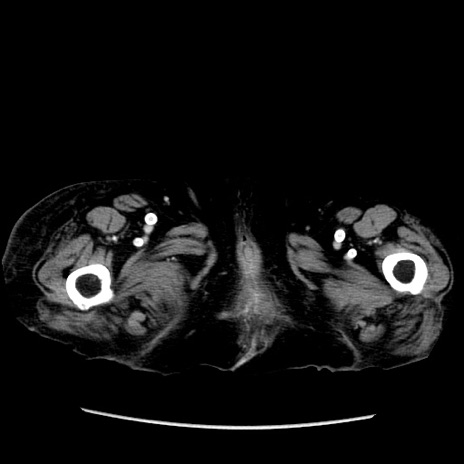

症例14(横断像)

【症例】 90歳代女性

【主訴】 腹痛・嘔吐

【現病歴】今朝から左側腹部痛を認めた。 経過観察していたが、嘔吐を認めたため来院。

【既往歴】 子宮癌術後

【身体所見】 意識清明、BP 127/54mmHg、P 98bpm Sp02 95%(RA)、BT 35.8°C、腹部平坦・軟腸ぜん動音聴取良好、右下腹部圧痛(+) 反跳痛なし

【データ】WBC 9800、CRP 0.46